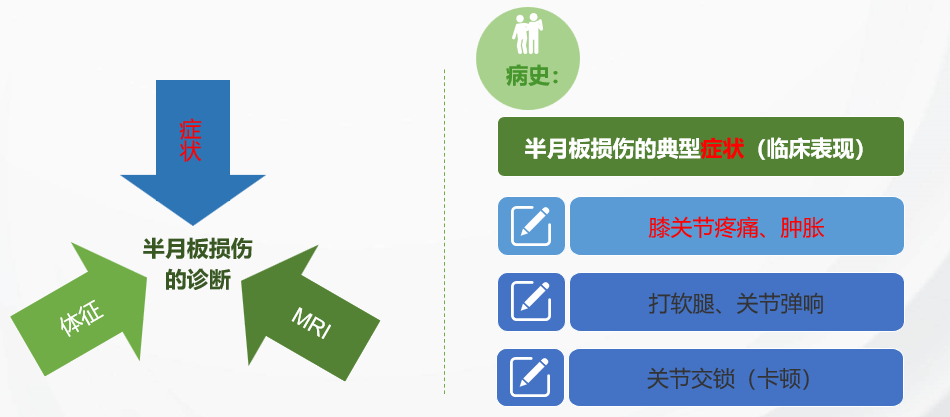

【半月板损伤的诊断】

诊断之一:症状

诊断之二:体征

诊断之三:MRI